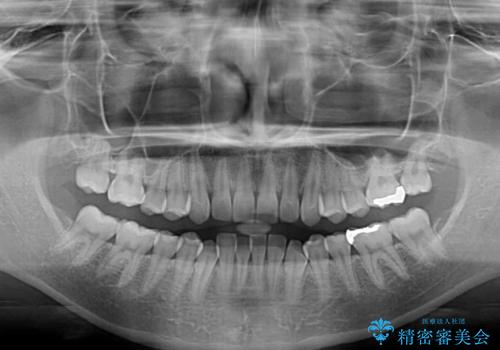

下顎前歯にデコボコが集中していたため、顎間ゴムによる後方移動とIPR(歯と歯の間を削ること)により歯列を整えることとしました。

下顎前歯のデコボコが集中しており、奥歯の咬み合わせは、上顎に対して下顎が前方位にある状態でした。下顎の歯列を後方へ移動させる治療はインビザラインの得意とするところですので、1年程度で無事に治療を終えることができました。